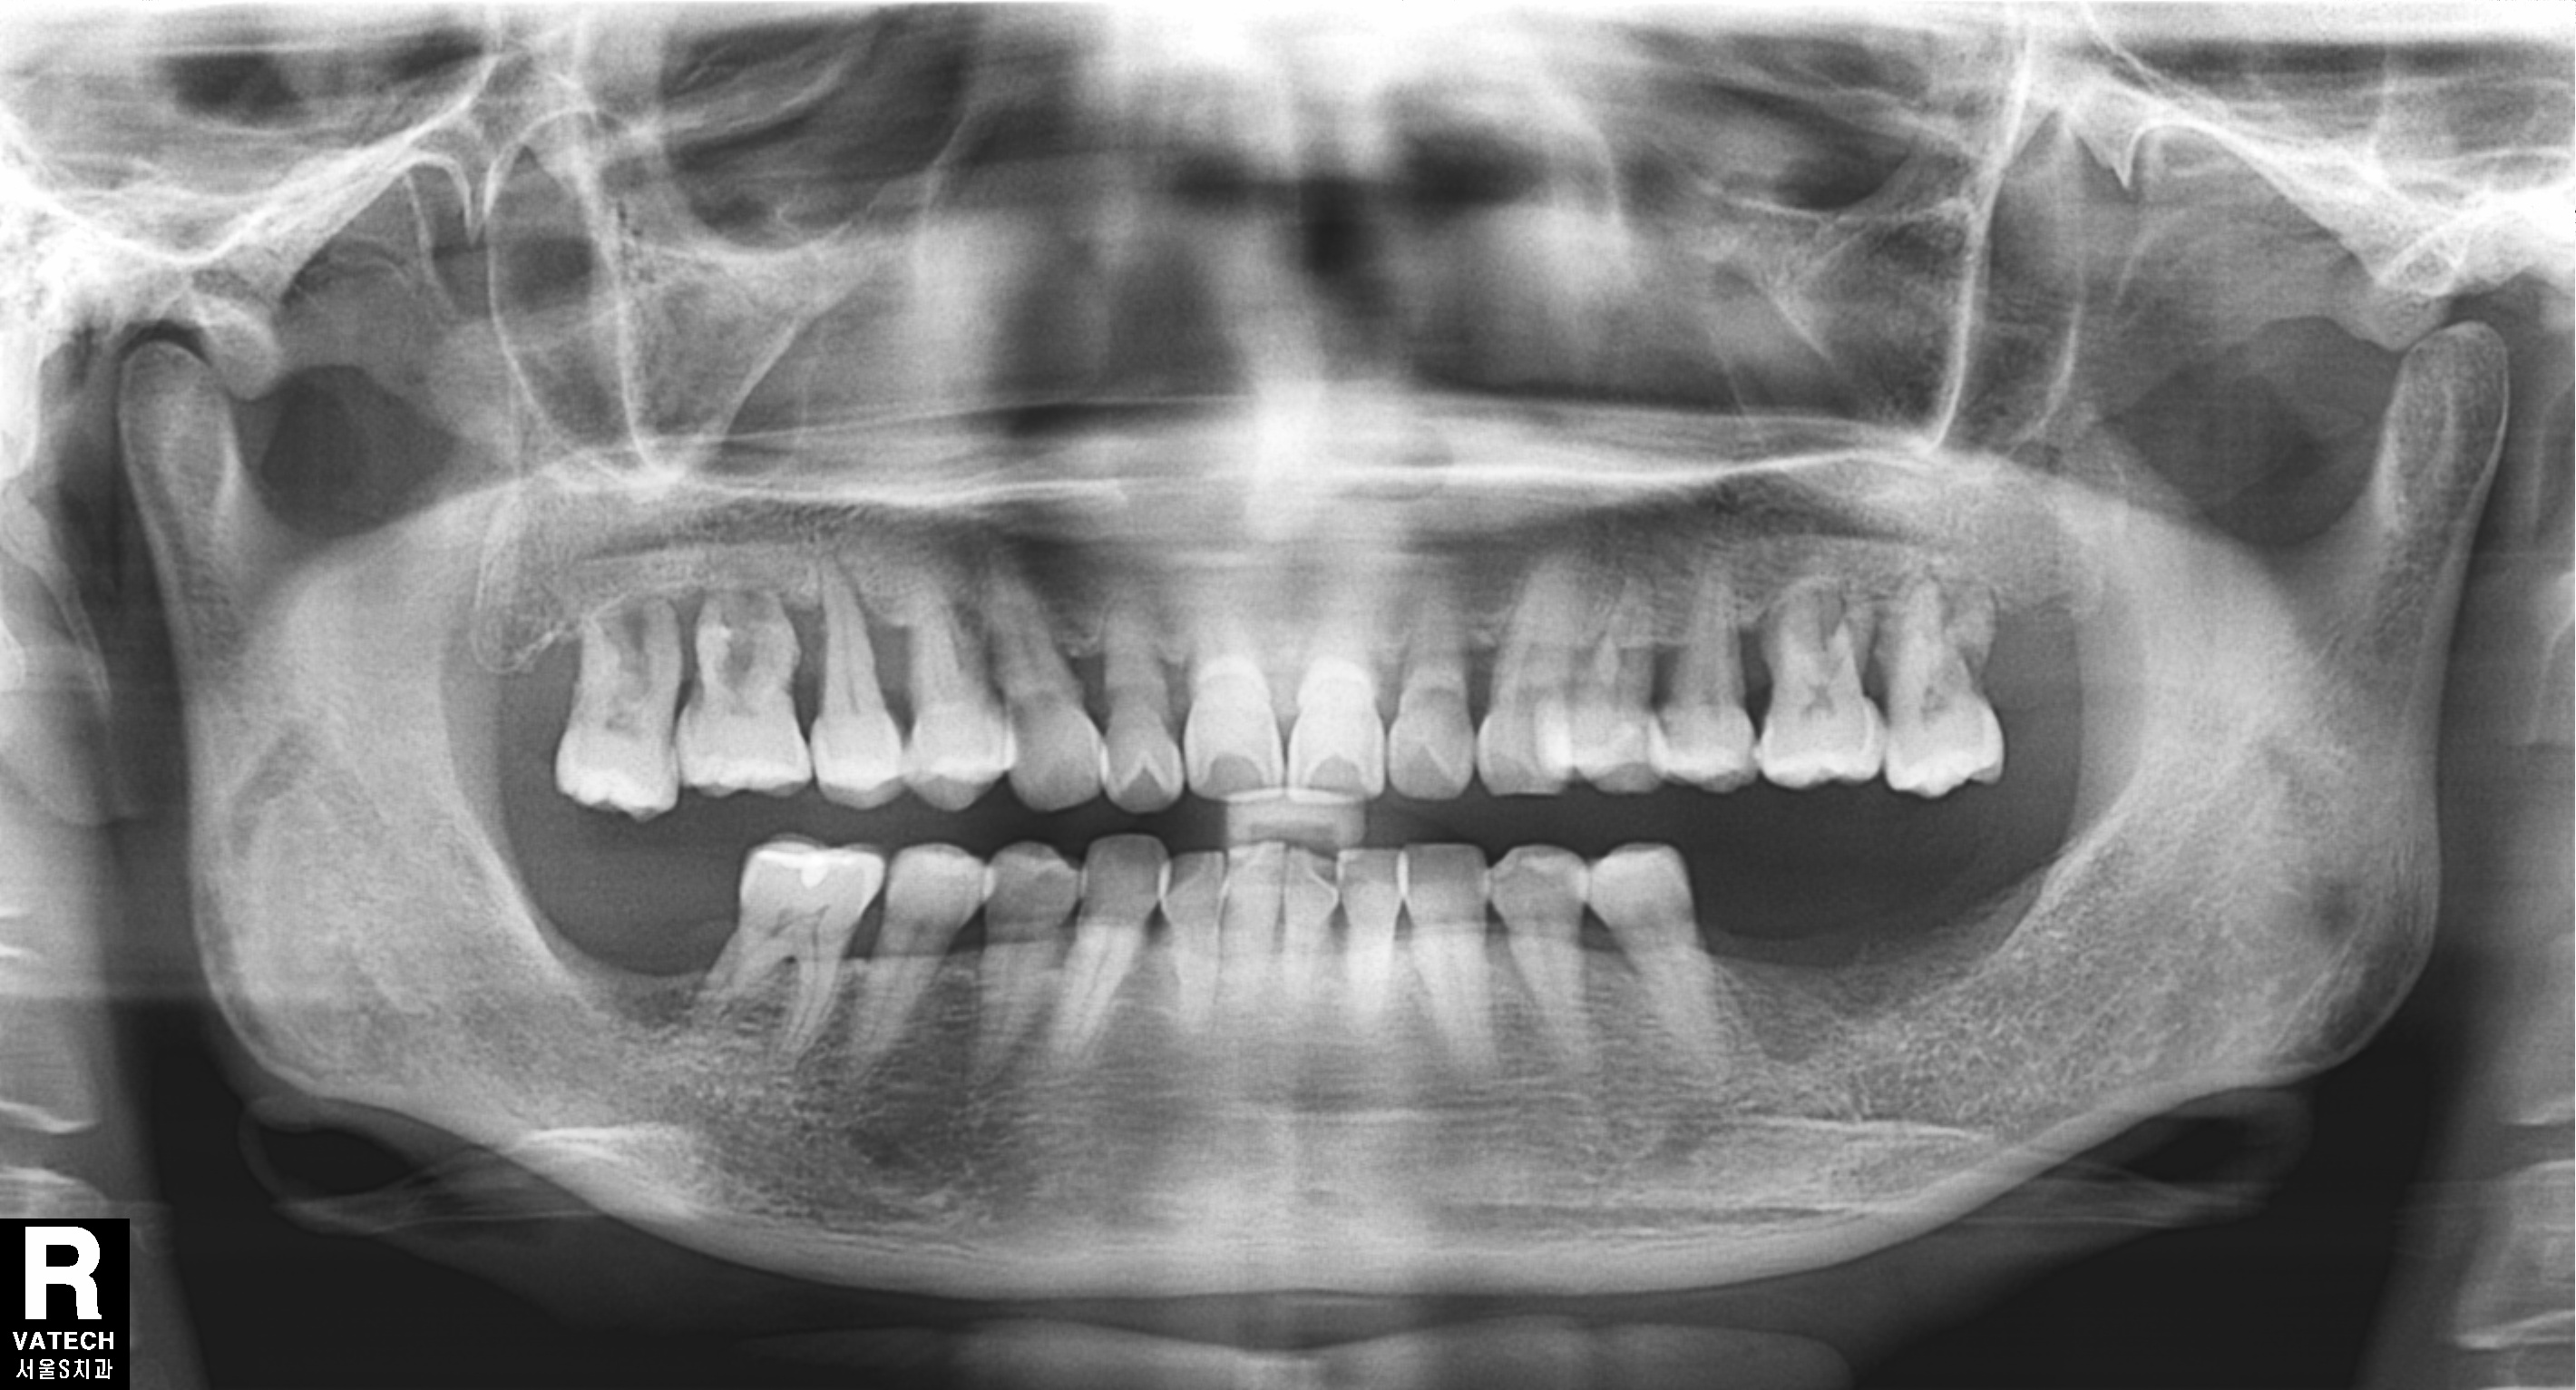

오랜 기간 아래 어금니가 없이 지내셨던 50대 여성분이 김포 서울케이치과에 내원 하셨습니다.

검진을 해보니 위에 양쪽 어금니가 많이 내려와 있고 치주염이 심하여 흔들리고 있었습니다.

치아를 살리기에는 이미 늦은 상태로 발치 후 임플란트로 치료 계획을 세웠습니다.

<처음 상태>

파노라마 엑스레이와 구내 사진에서 보듯이 위에 양쪽 어금니는 모두 발치가 필요한 상태입니다.